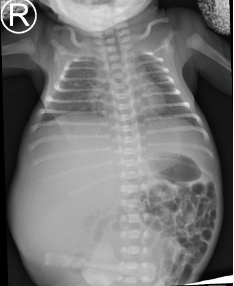

Preterm premature rupture of membranes (pPROM) before 22–24 weeks of gestation is considered previable and poses a high risk to the chances of successful delivery. Multicystic dysplastic kidney (MCDK) is the most common form of dysplasia of this organ, usually affecting 1 kidney. A prenatal suspicion of MCDK requires escalation of the clinical process to a reference center qualified and equipped for further diagnosis and treatment. We present a unique case of prenatal pPROM at 19 weeks of gestation in a pregnancy complicated by fetal MCDK as an interesting obstetric and neonatal patient story. We have not found any published evidence on the impact of coexisting fetal congenital malformations on a pregnancy affected by previable pPROM.

Balasundaram M, Chock VY, Wu HY, Blumenfeld YJ, Hintz SR. Predictors of poor neonatal outcomes in prenatally diagnosed multicystic dysplastic kidney disease. J Perinatol 2018;38(6):658-64.